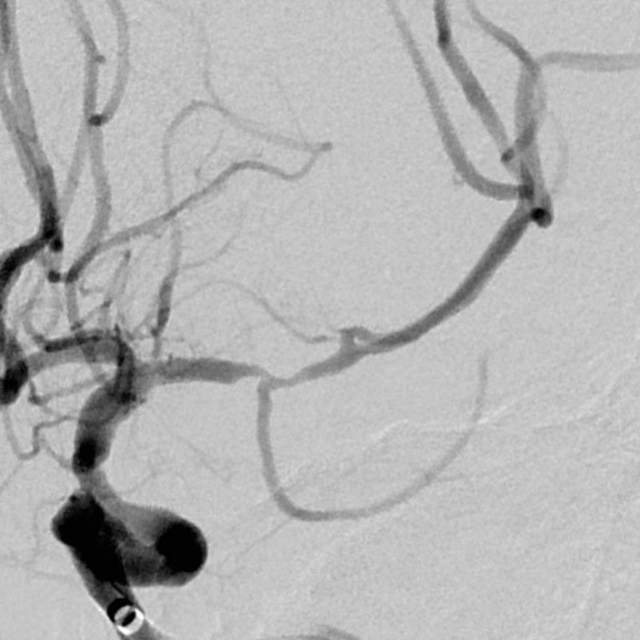

1、第一个患者:我们给予一期外科干预后,一个月后检查发现,狭窄的部位比术后即刻有改善,继续药物治疗,暂时无需手术,出院继续随访;

术前

术后即刻

一个月后随访好转,继续观察